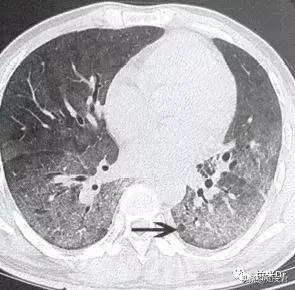

3.肺孢子菌肺炎(PCP)

PCP是由耶氏肺孢子菌引起的肺部感染性疾病,在艾滋病患者中极为常见,也是患者死亡的主要原因。在首次确诊的艾滋病患者中,PCP发生率为70~80%,病死率高达20~40%。90%的PCP发生在CD4+T细胞计数<200个/μl的患者中。典型表现包括:

发热

干咳

进行性呼吸困难

低氧血症